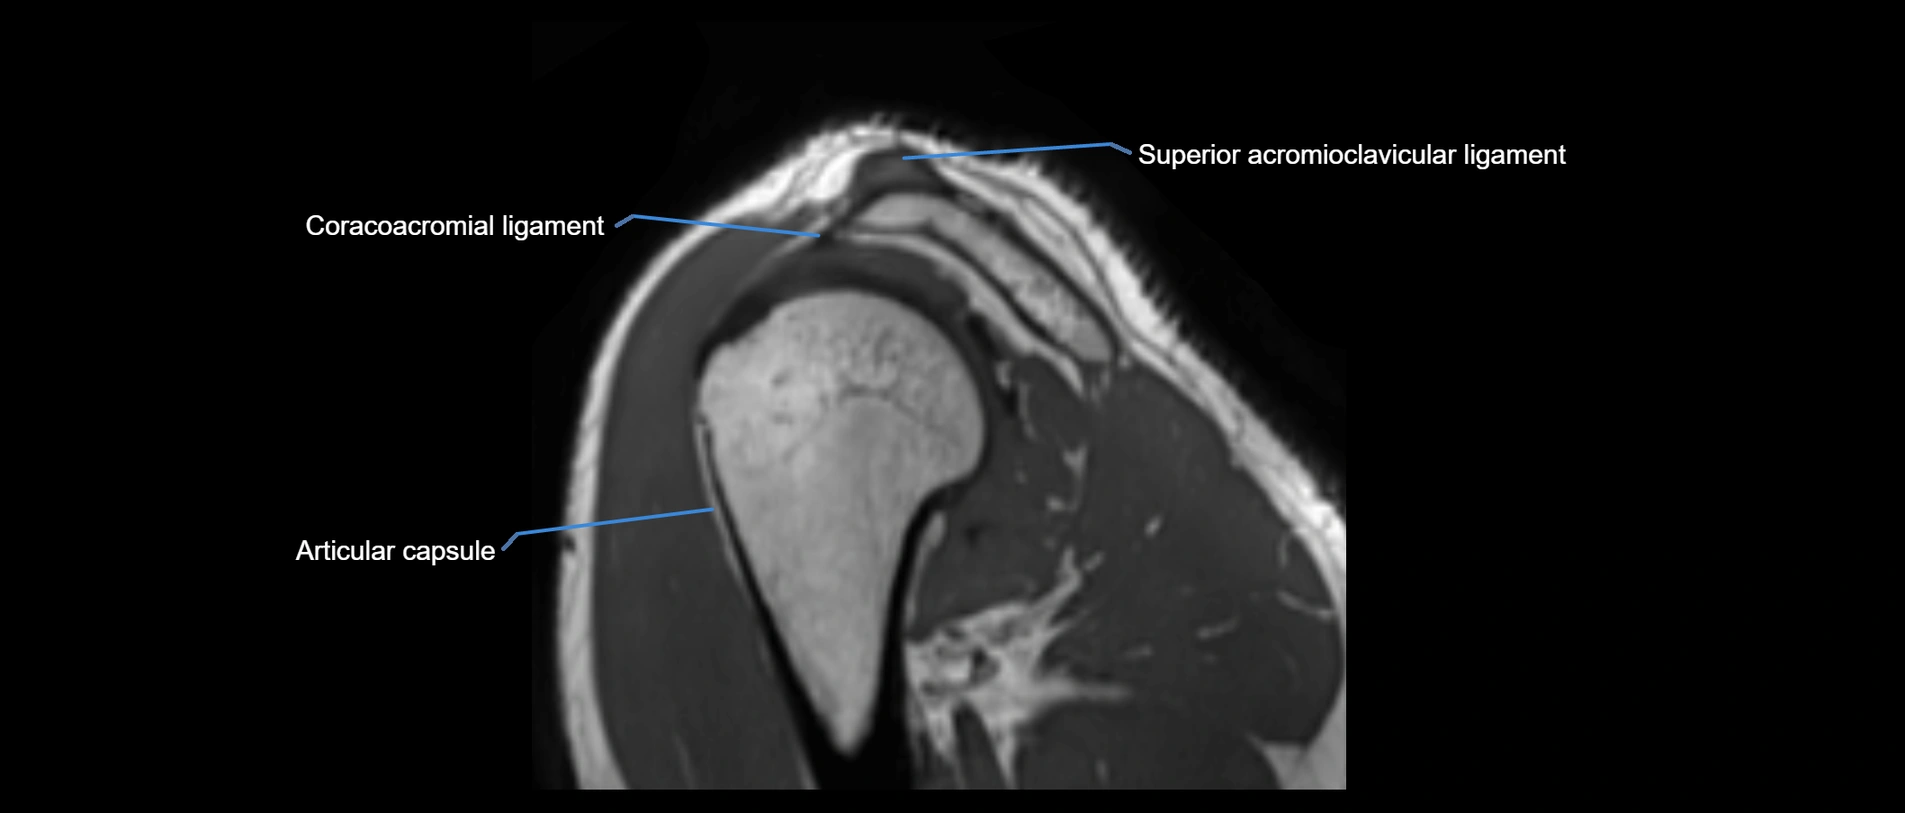

MRI images

image

MRI Appearance

• T1-weighted images:

• Normal ligament: Low signal (dark linear band) spanning acromion to clavicle.

• Surrounding fat planes: Bright, delineating the ligament clearly.

• Marrow of clavicle and acromion: Bright due to fatty content.

• Tears: Discontinuity or irregular thickening with intermediate-to-bright signal.

• Chronic injury: Thinning, fraying, or irregular low-signal fibers with adjacent scarring.

• T2-weighted images:

• Normal ligament: Low signal, homogeneous.

• Partial tear or sprain: Focal hyperintensity or thickening.

• Complete tear: Discontinuity with fluid-bright gap between clavicle and acromion.

• Associated edema: Bright signal in distal clavicle or acromion marrow.